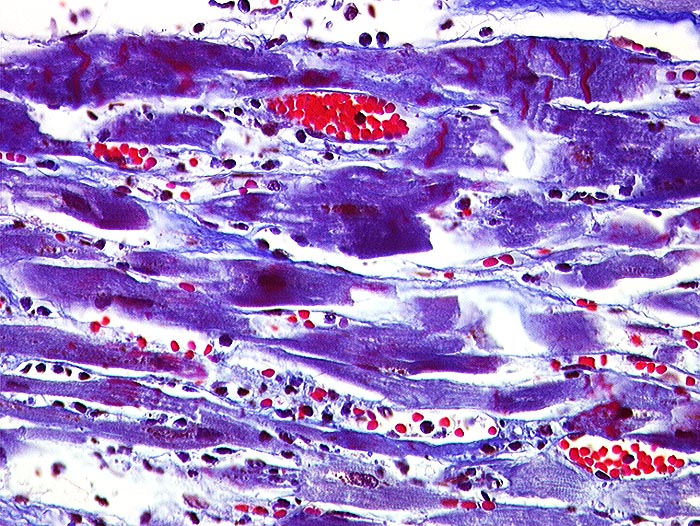

Makroskopie

Pathologischer Befund